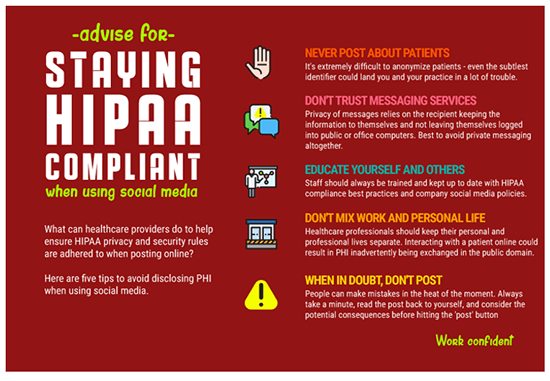

The key to preserving confidentiality is to allow only authorized individuals to have access to information. This begins with authorizing users based on pre-established role-based privileges. The administrator identifies the user, determines the level of information be shared and assigns usernames and passwords. The user should be aware that they will be accountable for the use and misuse of the information they view and only have access to the information they need to carry out their responsibilities. Hence assigning user privileges is a major aspect of medical record security. Always remember HIPAA as you were taught in your radiography program.